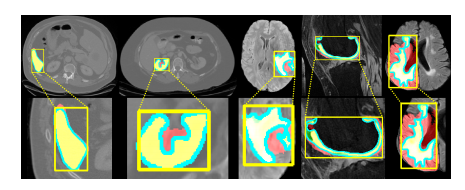

Fig. 15: Relationship between DICE and FO. From left to right, FO gradually increases. The yellow box represents the box prompt, the red mask is the pre diction, the green mask is the GT, the yellow mask is the overlap of prediction and GT, and the blue contour is decoded from the Fourier series.

图15:DICE与FO之间的关系。从左到右,FO逐渐增加。黄色框代表框提示,红色掩模是预测,绿色掩模是真实标注(GT),黄色掩模是预测和真实标注的重叠部分,蓝色轮廓是从傅里叶级数解码得到的。